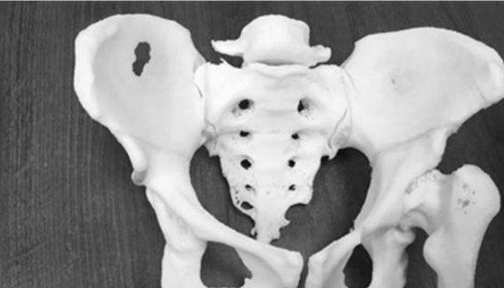

河南治疗骨科医院:股骨头坏死如何进行功能锻炼?

河南治疗骨科医院介绍当我们已经明确存在股骨头坏死时,而且我们了解我们股骨头坏死的程度…[详情]